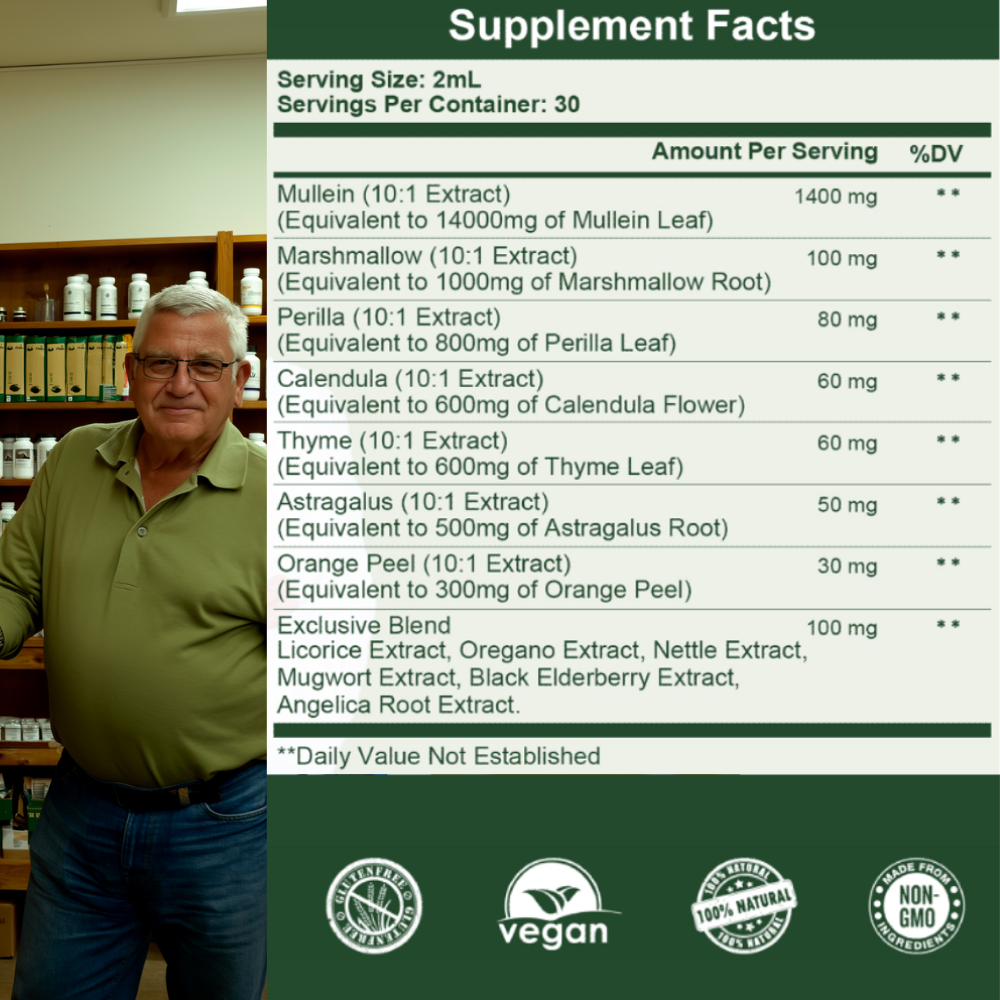

Breaks the panic cycle, restores natural breathing, and helps repair your lungs — giving you back your second chance at life.